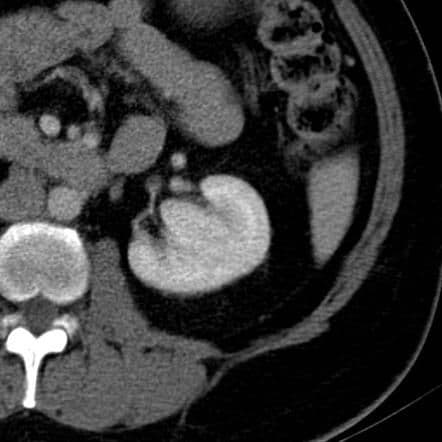

4. Hipertrofia de la Columna de Bertin: el diagnóstico del caso que hemos presentado. Es muy frecuente. Consiste en tejido cortical normal que protruye hacia el seno y se ubica entre dos pirámides medulares. Su ecogenicidad es la misma que la del parénquima renal. En el modo Doppler color, no captará.